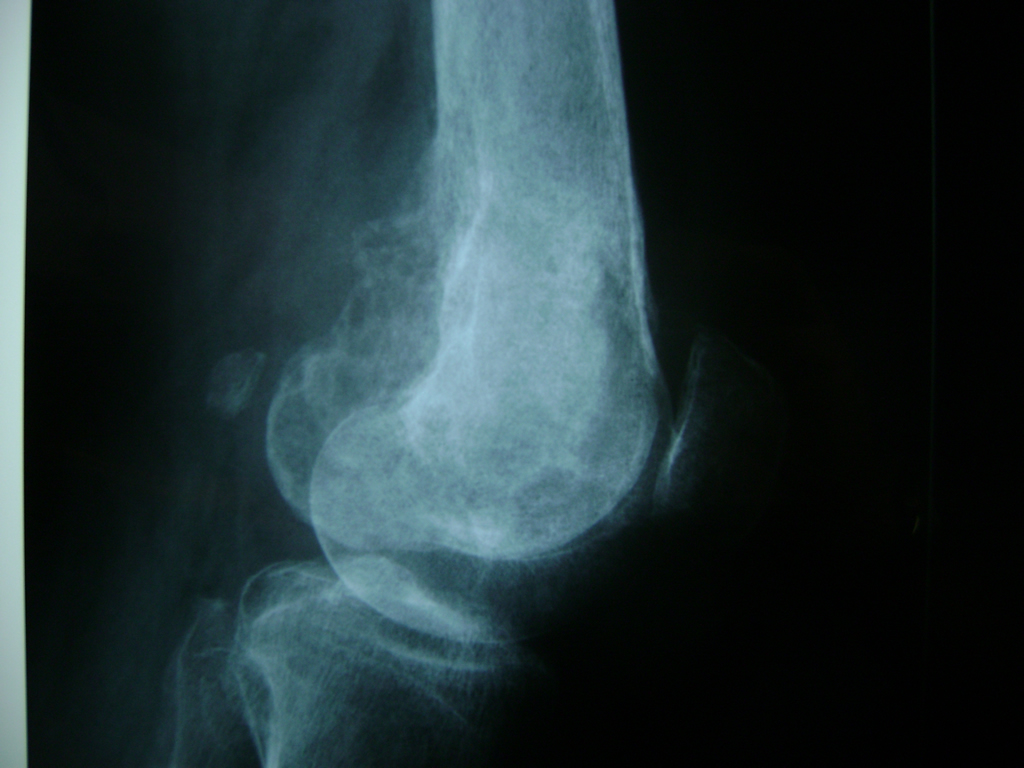

Cirugías de Codos - Rodilla

La artroscopia de rodilla es un cirugía en el cual la estructura interna de la articulación es examinada ya sea para realizar un diagnostico o para realizar un tratamiento, este procedimiento se realiza utilizando un instrumento parecido a un pequeño tubo llamado artroscopio.